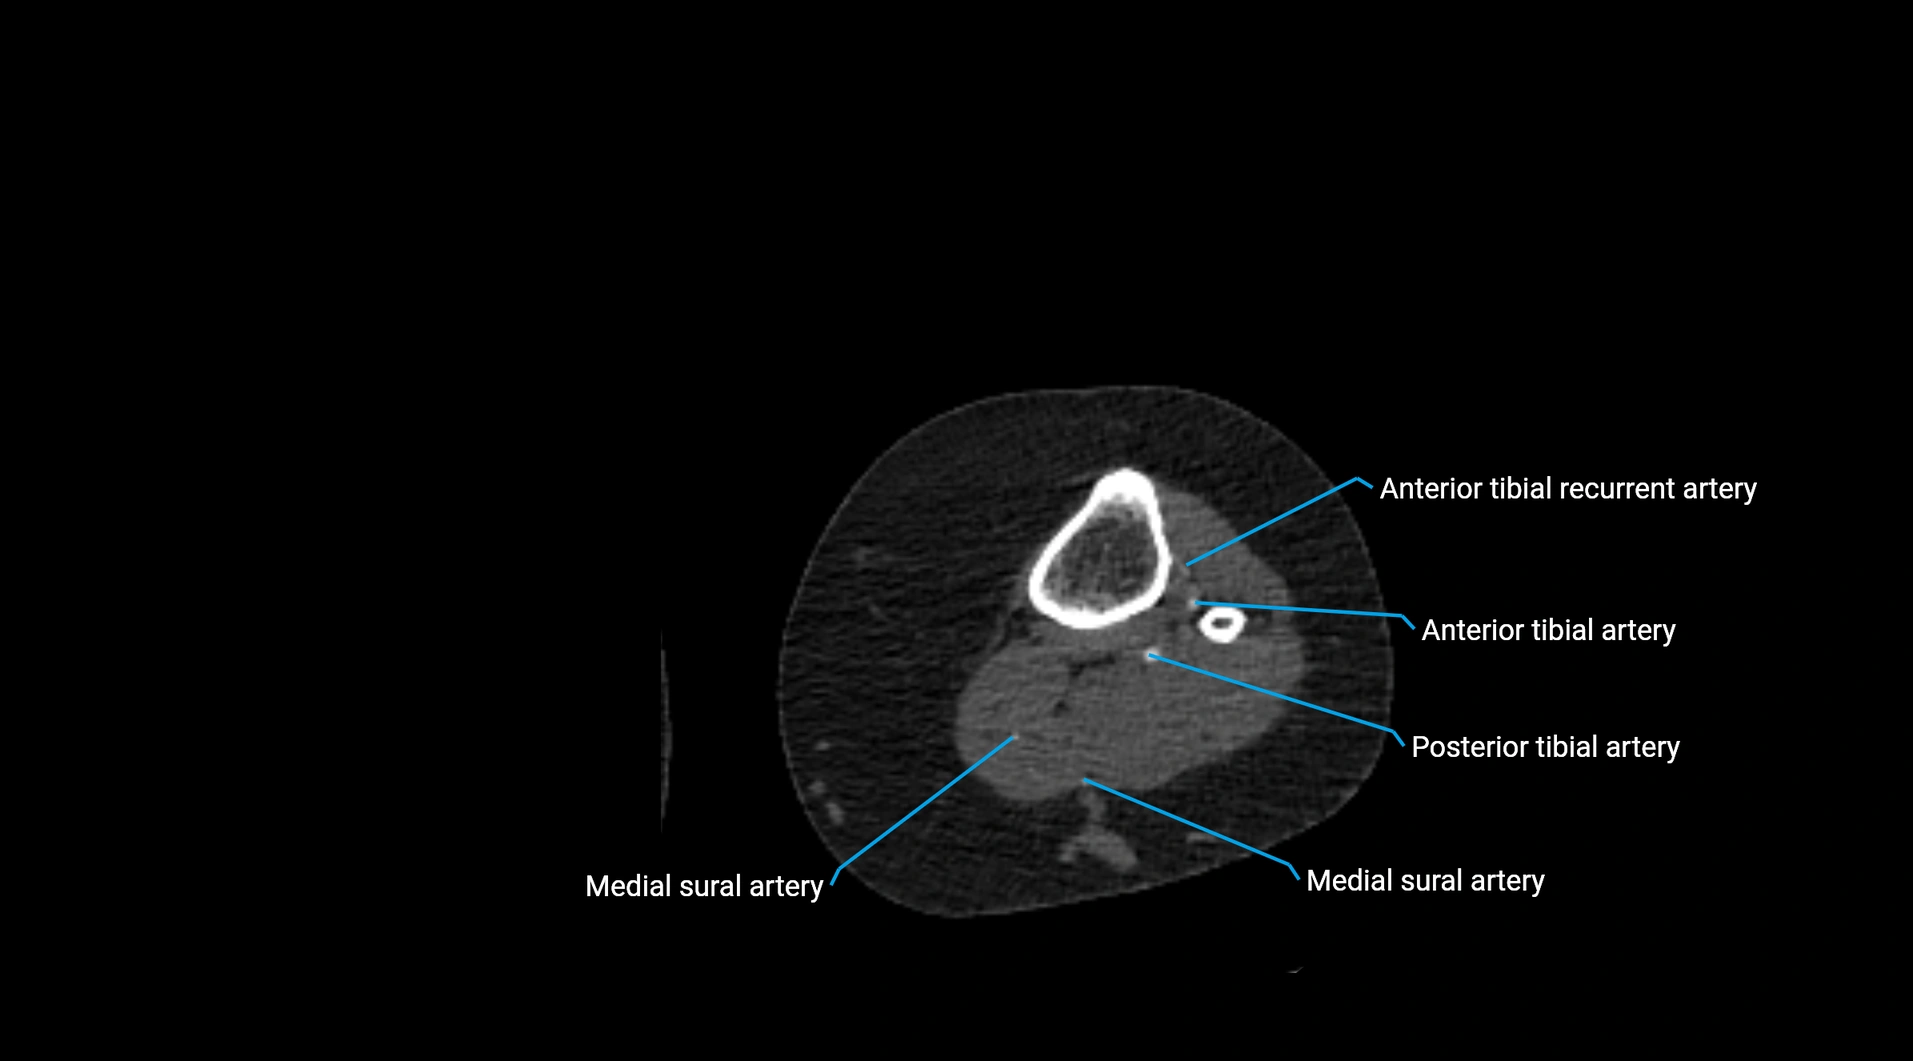

CT images

image